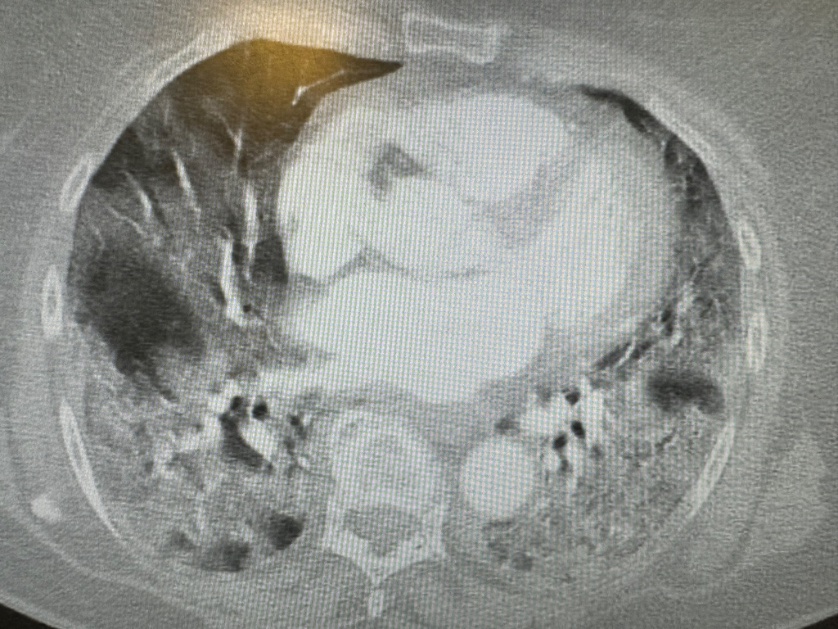

#medizin #notfall Was fällt Euch dazu ein?